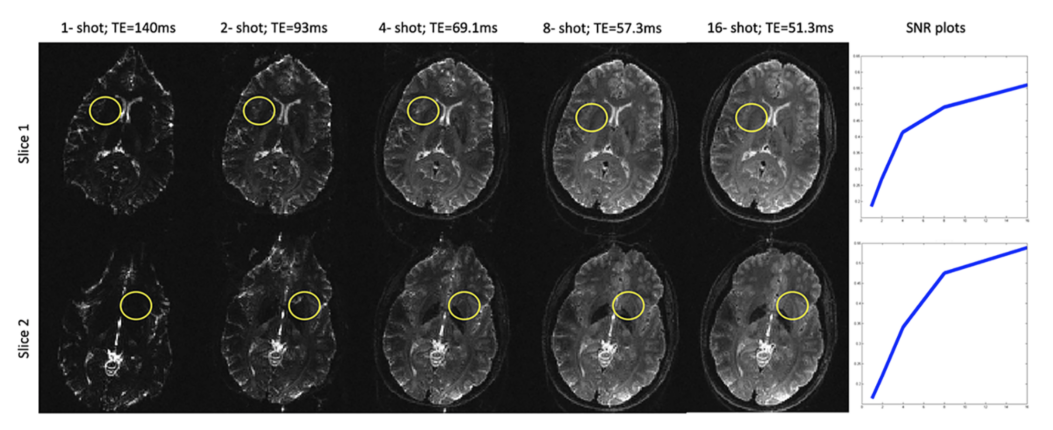

Figure 4 demonstrates the effect of TE on image quality of the DWIs collected at 7 Tesla. Because of the short T2 relaxation times at higher field strengths, shorter TEs becomes extremely desirable for studies at higher field strengths. 4-shot or higher number of shots provide good SNR and provide a significant reduction in the TE. As a result, susceptibility related artifacts are also minimized. The MUSE method has been shown to be effective in unaliasing the motion-induced ghosting artifacts for a 4-shot DWI acquisition when good phase estimates are available (26). For this reason, we implemented the MUSE method and we compare the proposed reconstruction with this method. For the purpose of comparing with the proposed regularized reconstruction, which included a smoothness constraint, the MUSE algorithm also included an iterative reconstruction using the TV constraint.

Fig 4: Effect of long echo times at 7T demonstrated on non-diffusion weighted images collected using different number of shots for a 128 x 128 acquisition matrix. Due to the shortened T2 relaxation times, high signal drop-out are observed in many regions of the single and two-shot acquisitions as pointed out by the circles. The SNR computed from the ROIs as a function of the number of shots are shown in the last column. No parallel imaging acceleration was employed in these acquisitions. However, with single-shot imaging, it is common to employ parallel imaging acceleration of at least 2, in which case, the TE becomes comparable to the 2-shot case in column two.